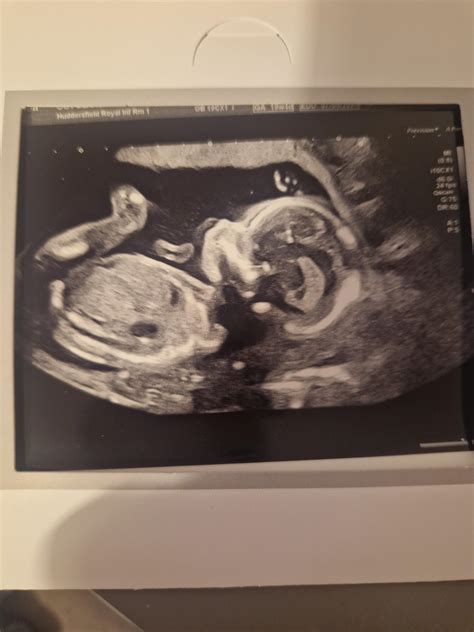

Okay, first things first, let’s talk about what the 20-week scan actually is. This isn’t just a fun sneak peek at your baby (though, let’s be honest, that’s a major perk!). The 20-week scan is a crucial medical appointment that provides a detailed look at your baby’s development. It’s a comprehensive ultrasound examination that typically takes place between 18 and 21 weeks of pregnancy. The main goal? To assess your baby’s physical development and identify any potential abnormalities. During the scan, the sonographer will check everything from the baby’s brain and spine to their heart, kidneys, and limbs. They’re essentially doing a full body check-up while your little one is still cozy inside! It’s also a chance to confirm the baby’s sex, if you want to know, and to check the position of the placenta. This scan is really thorough, and it’s designed to give you and your healthcare team as much information as possible about your baby’s health. Now, I know, hearing about all the things they check can sound a bit scary, but remember, the vast majority of scans come back with good news. Think of it as a super-detailed health check to ensure everything is progressing as it should. It’s a proactive step in ensuring the well-being of both you and your baby.

Now, let’s tackle the elephant in the room: the potential for bad news. It’s completely normal to worry about this, and many expectant parents find themselves searching online for information and experiences. Forums like OSCIPSEC, HowSc, and Reddit can be both a blessing and a curse. On one hand, they offer a sense of community and shared experiences; you can connect with others who are going through the same thing. On the other hand, they can also be a breeding ground for anxiety, as you might come across stories that are particularly worrisome. So, what kind of issues can be detected at a 20-week scan? Well, sonographers are looking for a range of potential problems, from minor issues that may resolve on their own to more serious conditions that require further investigation and intervention. These can include structural abnormalities, such as heart defects, spina bifida, or cleft lip and palate. They also check for markers that could indicate chromosomal abnormalities, such as Down syndrome. It’s important to understand that finding a marker doesn’t necessarily mean there’s a problem; it just means that further testing might be recommended. Sometimes, the scan might reveal issues with the placenta or amniotic fluid levels, which can affect the baby’s growth and development. In some cases, the sonographer might not be able to get a clear view of certain structures, which could lead to a repeat scan being scheduled. This doesn’t always mean something is wrong; it could just be the baby’s position or other factors. Remember, while it’s good to be informed, try not to jump to conclusions based on what you read online. Every pregnancy is unique, and the best source of information is always your healthcare provider. They can provide personalized advice and support based on your specific situation.